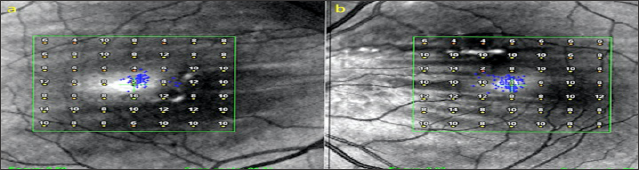

A 50 year old male presented with complaints of blurred vision. The VA was 9/10 in both eyes with no refractive correction need. Anterior segment biomicroscopic examinations were of course normal in both eyes. IOPs were 14 mmHg in both eyes. In the fundus examination, several angioid streaks and light-dark colored bands were seen in the per papillary region in both eyes (Figure 5a & 5b). Wrinkles were observed in choroid, RPE and neurosensory layers in OCT (Figure 6a & 6b). In FFA, more prominent angioid streaks were observed around the optic disc in the left eye, and hyper fluorescence due to RPE cracks was observed (Figure 7a & 7b). Microperimetry (MP) revealed that sensitivity was normal in folding areas while sensitivity was decreased in areaswith RPE defect (Figure 8a & 8b). Radiologic imaging studies and laboratory examinations for orbital, intracranial and systemic pathologies were within normal limits. CFs associated with angioid streaks was diagnosed.

Figure 8: Microperimetry (a,b).